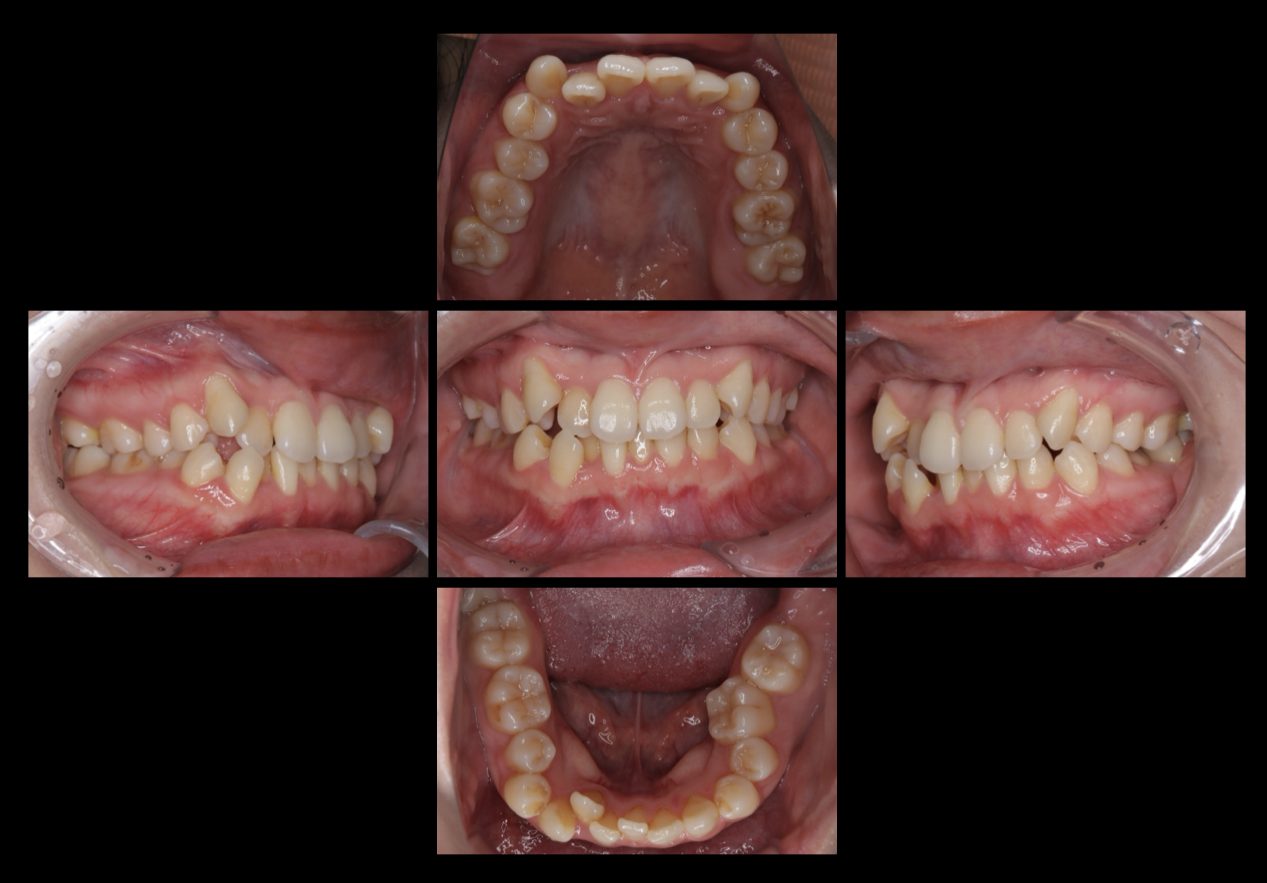

治療が終了した時の写真です。

歯列不正も無くなり、正中の傾きも改善され口元がスッキリしました。

卒業式までに治療を終わることができたのでよかったです。と満足して頂きました。